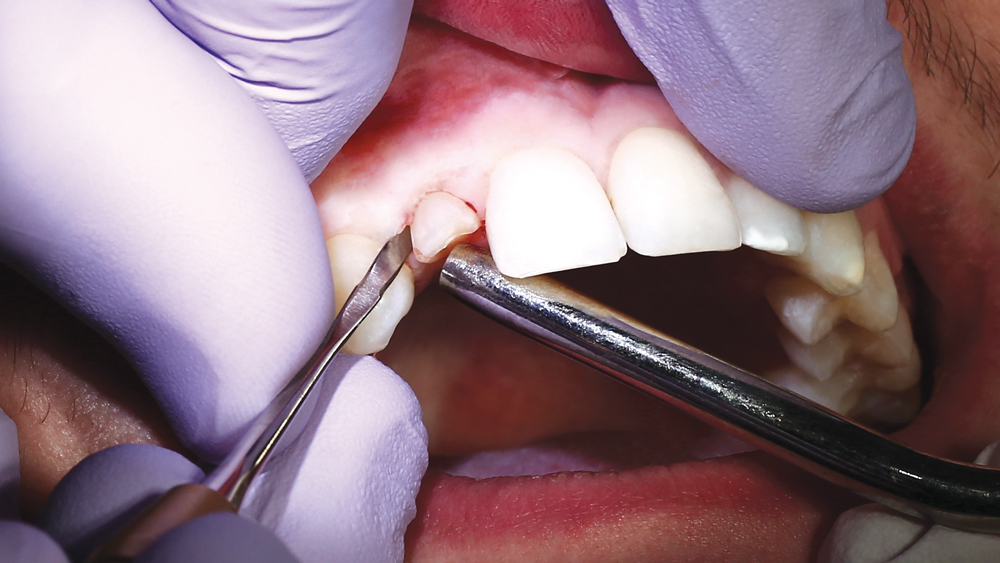

The following case illustrates the efficient, straightforward clinical workflow for placing Hahn Tapered Implants via guided surgery. A digital treatment plan is developed in which a 3.5 mm implant is positioned to support the ideal prosthetic outcome. An immediate provisional crown is designed in concert with the surgical guide and delivered at the time of surgery, helping to produce a predictable, highly esthetic restoration for a demanding case in the smile zone.